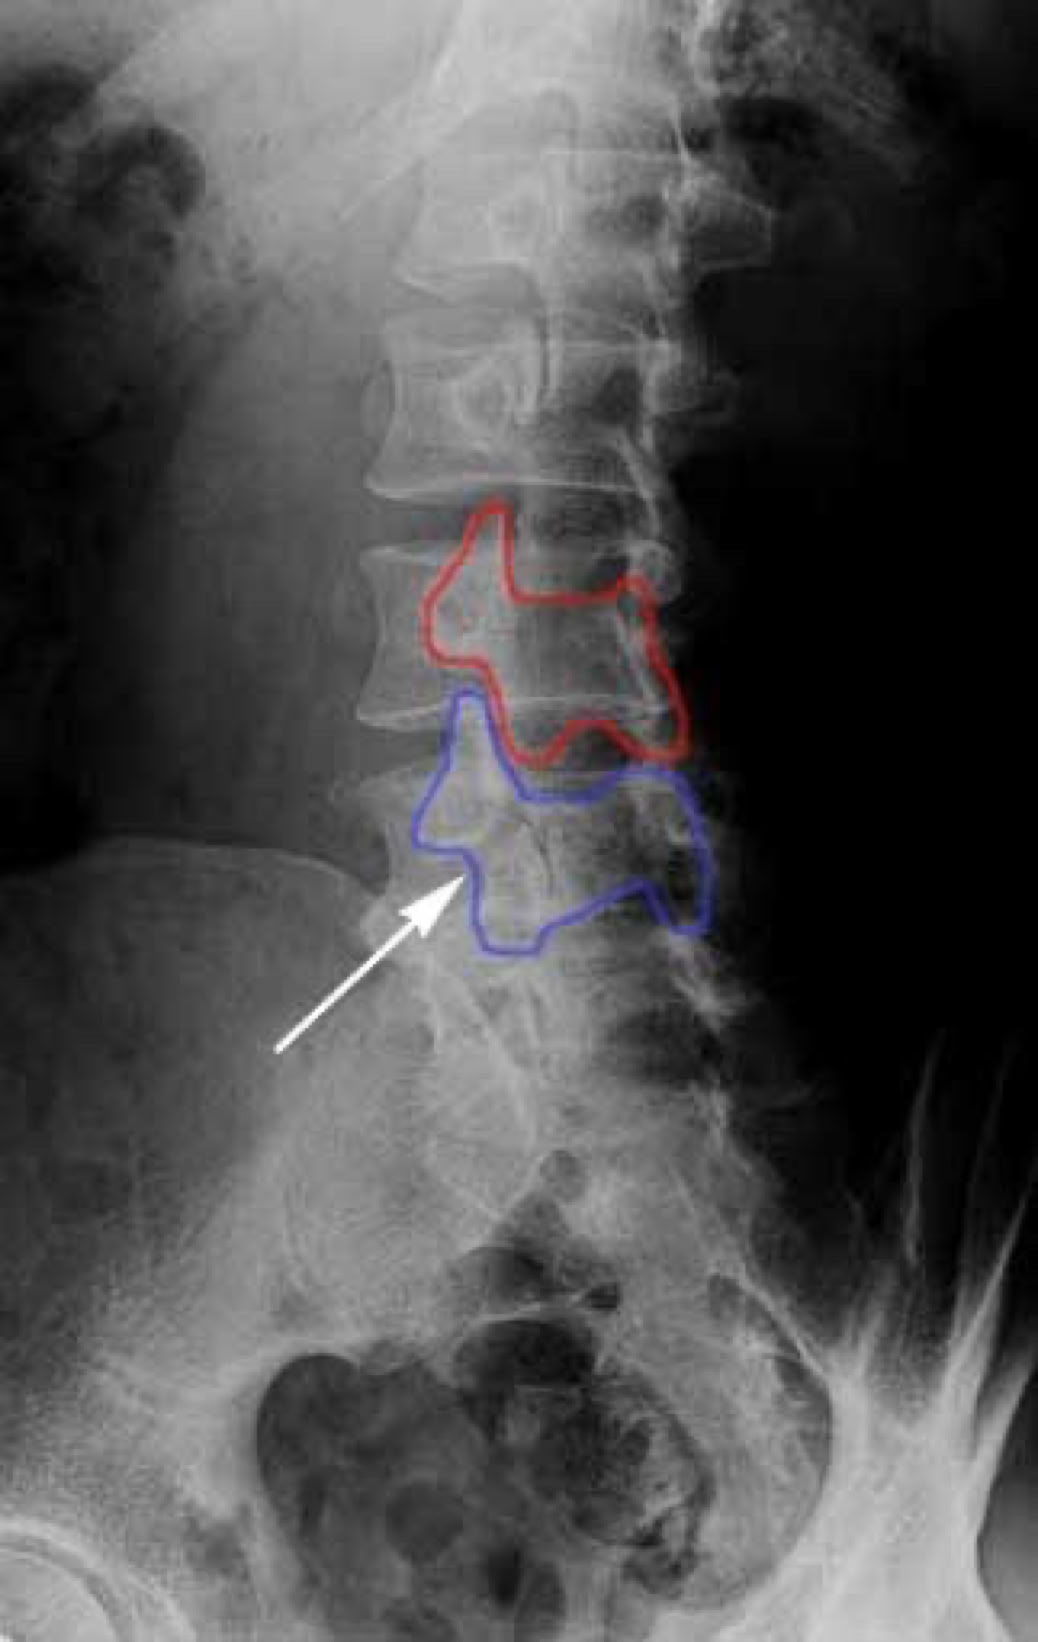

spondylolysis and spondylolisthesis

When we look at the spine from the side, we can imagine a scotty dog. It is outlined above. The pars fracture is seen as a collar around the dog's neck. Instability and movement can cause the neck to widen. We will see this below in an X-ray example.

pars on an xrays or as we call it scotty dog